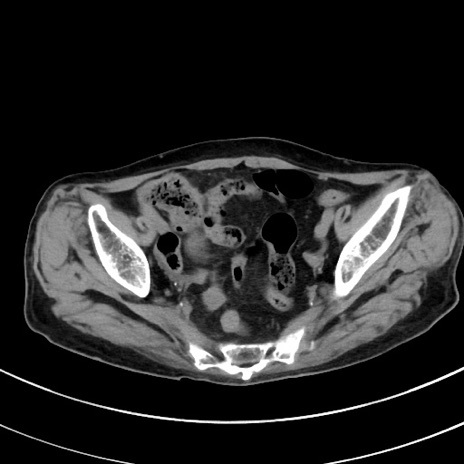

症例33(横断像)

【症例】70歳代 女性

【主訴】心窩部痛

【現病歴】延髄病変の精査・加療にて神経内科入院中。本日より心窩部痛あり。

【既往歴】虫垂炎

【身体所見】右下腹部を中心に圧痛と反跳痛あり。

【データ】WBC 10900、CRP 0.02